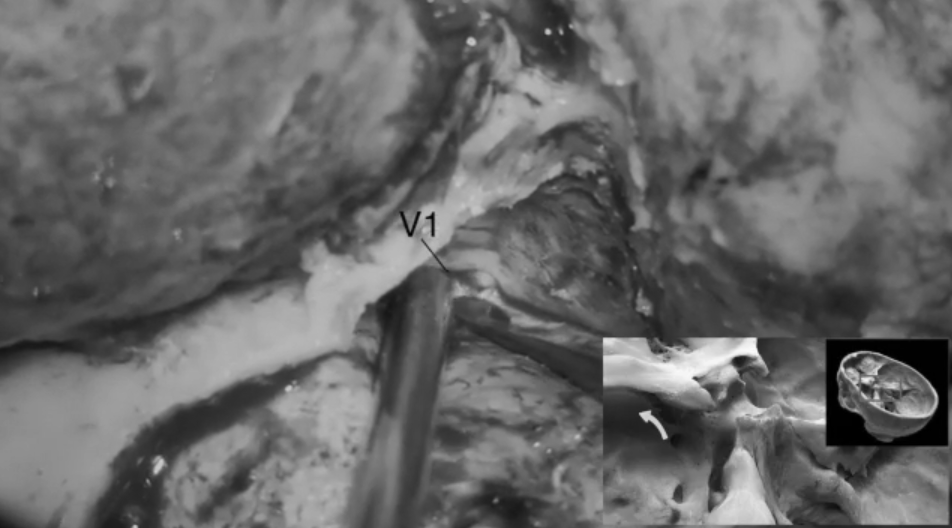

定位三叉神經(jīng)V1段,以助顯露眶上裂;游離并進(jìn)一步解剖眶上裂,識別、電凝并切斷眶腦膜韌帶。